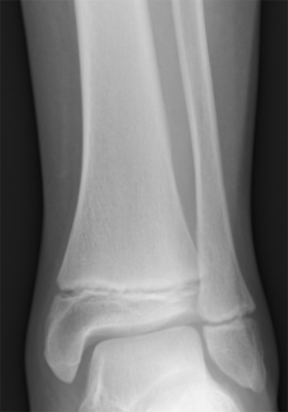

The size of a bone can also help determine whether it belongs to a human. Adult human bones are larger than subadult or infant bones. However, another major difference between human adult bones and those of a young individual or infant human can be attributed to development and growth of the epiphyses (ends of the bone). The epiphyses of human subadult bones are not fused to the shaft (Figure 8.7). Therefore, if a bone is small and it is suspected to belong to a human subadult or infant, the epiphyses would not be fused. Many small animal bones appear very similar in form compared to adult human bones, but they are much too small to belong to an adult human. Yet they can be eliminated as subadult or infant bones if the epiphyses are fused to the shaft.